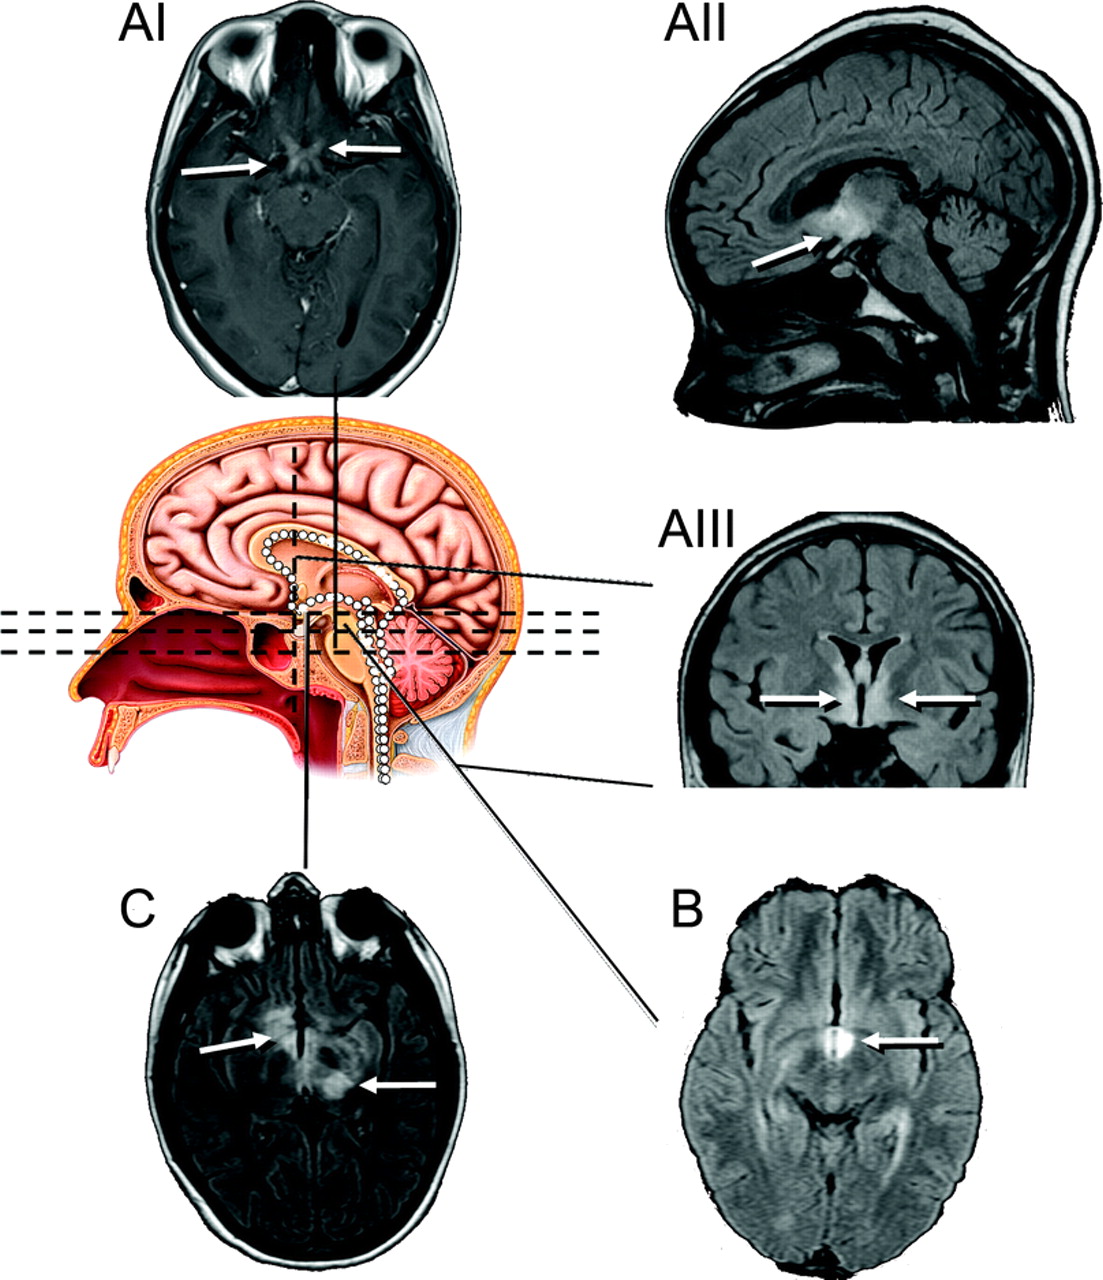

图1代表MRI异常与半球参与七个孩子的典型光谱中确定儿童中枢神经系统AQP4自身免疫

白色箭头表示异常液体衰减反转恢复(天赋)或T2信号。(一)病人1(8岁女孩展示与脑病)T2信号异常辐射触角的方式沿着Virchow-Robin空间通过顶叶皮层下白质从侧脑室。(B)病人2(12岁女童出现谵妄紧随其后昏迷,前面描述的14)主要支流白质异常。(我)病人3(15岁女孩出现谵妄和失语症)主要支流白质异常;1年后,双时态皮层病变被认为(C-II);病人除了轻微认知正常表达性失语症(C-III)。(d - i)患者4(8岁女孩展示脑病和癫痫)触角从侧脑室白质异常辐射到额叶和顶叶白质。随访MRI 8年后(D-II和D-III)演示了持久化天赋异常和全球萎缩。(练习)病人5(17岁女孩与11年历史的脱髓鞘疾病)膝的支流T2异常超过胼胝体压部;图片3年后揭示解决膝损伤(E-II)和脑积水(分流的;看到图3中,A和B)。(f i)患者6(15岁男孩出现脑病,焦点运动发作,和轻偏瘫)天赋信号异常在左侧中央颞区和大脑脚离开了。图片3年后(F-II)展示持久化天赋异常和左海马萎缩。